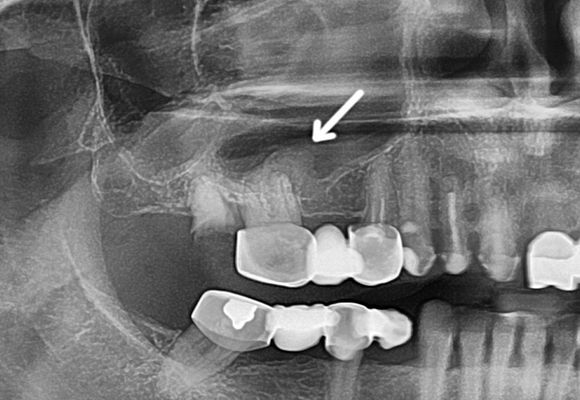

Під час діагностики одонтогенного гаймориту лікар повинен звернути особливу увагу на наявність зубних пломб, імплантатів і карієсу. Оцінити стан пазух можна за допомогою рентгенологічного дослідження.

Щоб виявити приховані патології лікар може призначити ортопантомограму – знімок щелепи з зубами. По ньому можна побачити характерні ознаки одонтогенного гаймориту.